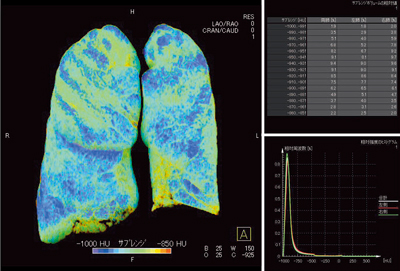

“lung parenchyma”の三次元表示では,左右のインクリメントごとの体積比率とヒストグラムが同時に得られるので,定量的な解析が可能である(図6)。

図6 症例1:肺気腫,GOLDU(parenchyma画像の三次元表示)

閾値と気腫肺量の関係(表1)では,Xe 10を閾値とすると,右肺26%,左肺29%の欠損域があることがわかる。これをCT値で分けると,−950〜−940HUあたりがXe 10と近い欠損域比率となる。閾値をXe 15に上げると,CT値と乖離した比率となることから,Xeの閾値の設定が今後の課題の1つとなるだろう。

表1 閾値と気腫肺量の関係